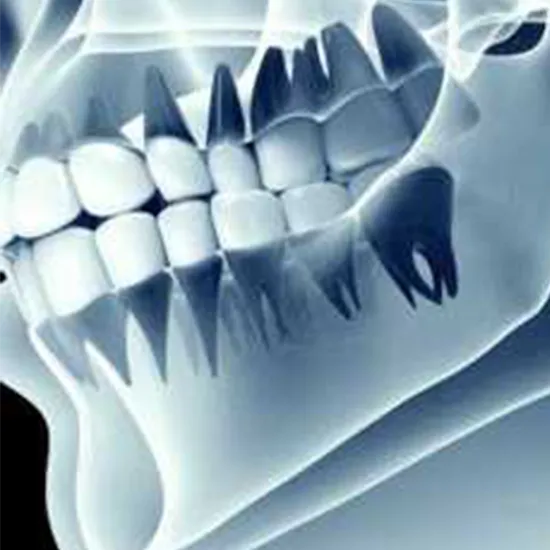

Panoramic TMJ X-ray is a diagnostic tool that uses X-Ray radiations to produce images of the Temporomandibular joint.

Panoramic TMJ tomograms usually image both condylar heads; the first patient is asked to sit or stand in front of an OPG X-ray machine. The technician will position a machine to take images of the X-Ray jaw from different angles. During the X-ray scanning arm is rotated in a semicircle around the patient's head, beginning on one side of the jaw and ending on the other.

A panoramic x-ray machine, rather than using film placed inside the mouth, projects a beam through the patient onto film or a detector rotating opposite the x-ray tube.